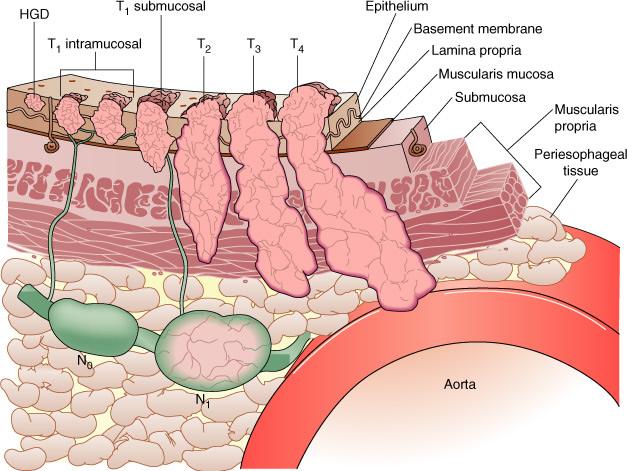

Na medida em que o tumor invade o órgão, aumenta o risco de invasão dos ductos linfáticos (em verde) e de causar metástase para os linfonodos (N0, N1, em verde). (associado à figura abaixo)